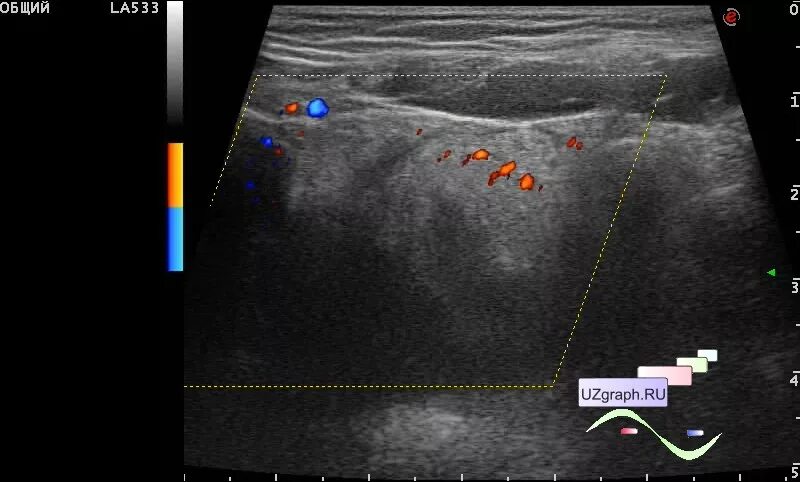

Абсцесс при аппендиците